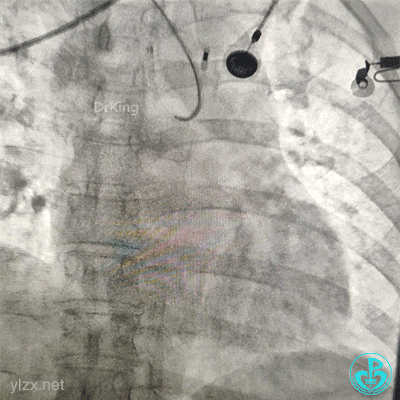

植入4.0×13mm支架1枚。

交换导丝后扩支架网眼。

结束手术。

下台时血压127/78mmHg,心率75次/分。